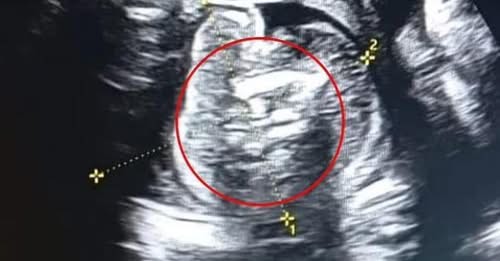

Ez a harmadik leggyakoribb rákos megbetegedés a világon

Az orvosok teljesen ledöbbentek.